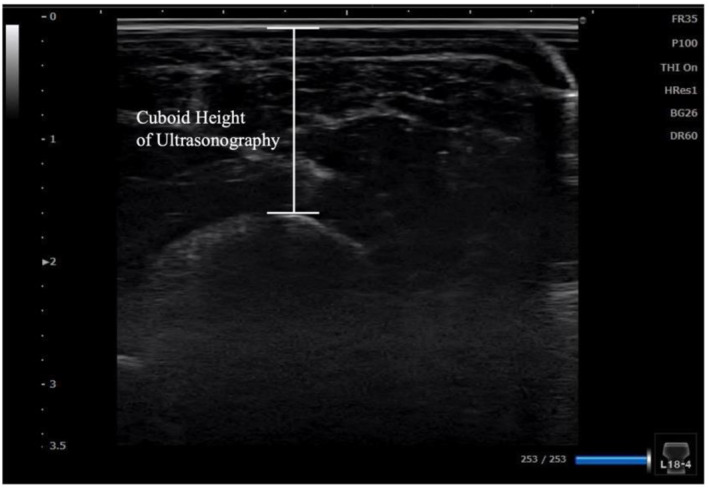

Introduction: The lateral longitudinal arch (LLA) is an essential structure of the foot. However, LLA evaluation methods remain underexplored compared to those of the medial longitudinal arch (MLA). This study sought to develop a method for measuring the cuboid height, the keystone of the LLA, using ultrasonography and to verify its correlation with radiography, as well as intrarater and interrater reliability.

Methods: This cross-sectional study included 21 university students (14 males and seven females). The cuboid height was measured using radiography and ultrasonography. The validity of ultrasonographic measurements was assessed through correlation with radiographic measurements and Bland-Altman analysis. Intrarater and interrater reliabilities were evaluated using intraclass correlation coefficients (ICCs).

Results: A strong correlation was observed between cuboid heights measured using radiography and ultrasonography (r = 0.98, p < 0.01). The Bland-Altman analysis revealed a fixed bias of -0.71 mm (95% confidence interval [95% CI]: -0.96 to -0.46 mm). Intrarater and interrater reliability for ultrasonographic measurements were almost perfect, with ICCs of 0.98 and 0.99, respectively.

Conclusions: Cuboid height measurements using ultrasonography demonstrated high validity and reliability. This method offers a noninvasive and cost-effective alternative to radiography, with potential clinical applications in the evaluation of LLA and related conditions such as cuboid syndrome and lateral foot injuries.